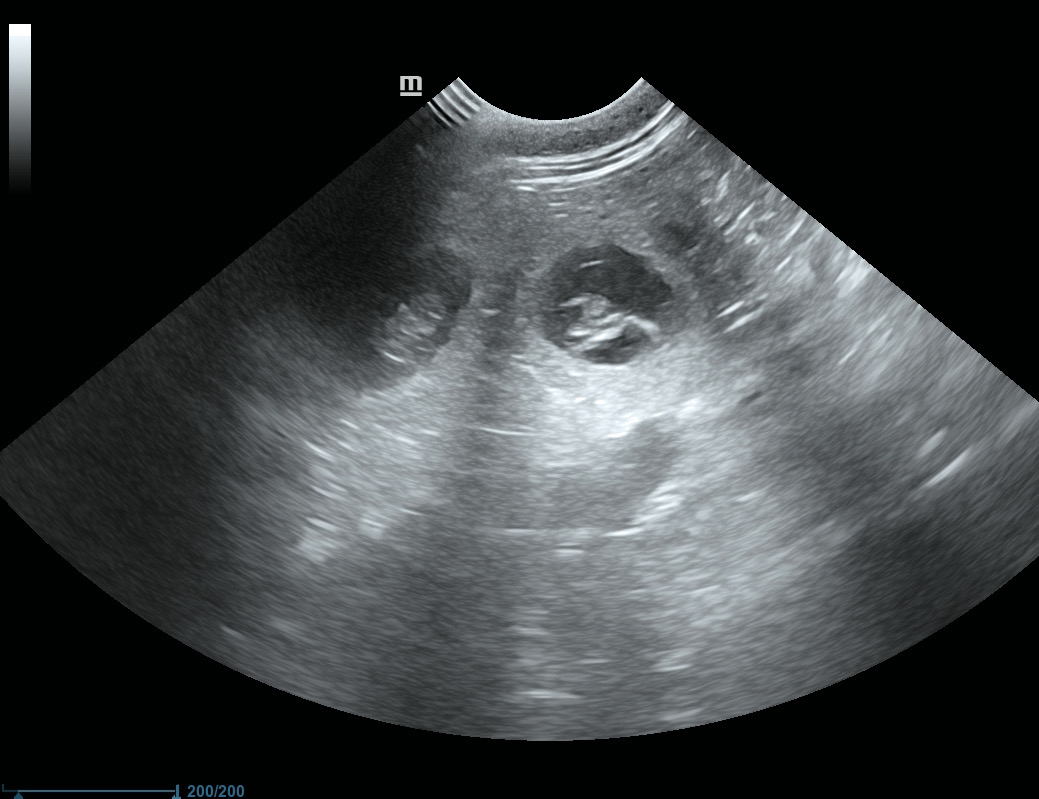

UltraSChall-Termin 15.9.2026 / 28.Tag der Trächtigkeit

Am 28. Tag nach dem ersten Decken wurden vom Tierarzt sechs Fruchtanlagen im Ultraschall gesehen.